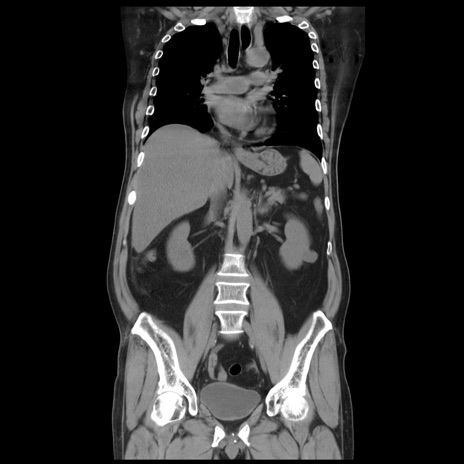

症例20(冠状断像)

【症例】 60歳代男性

【主訴】 腹部膨満、嘔吐

【現病歴】5日前頃より倦怠感を認め食事量減少し4日前の朝嘔吐、食事摂取困難となった。 3日前近医受診し点滴施行され整腸剤などを処方された。 当日他院を受診し、腹部膨満著明、炎症反応の上昇(CRP10.8、WBC11200)あり、紹介受診となる。

【身体所見】 意識JCS1 受け答えがはっきりしないBP 111/57mHg、 P 67bpm、、BT35.2°C、SpO2 97%(RA)、 腹部:膨隆、打診で鼓音あり、全体的に圧痛有り、腸蠕動音(-)、反跳痛ははっきりせず。

【データ】WBC 11400、CRP 14.20